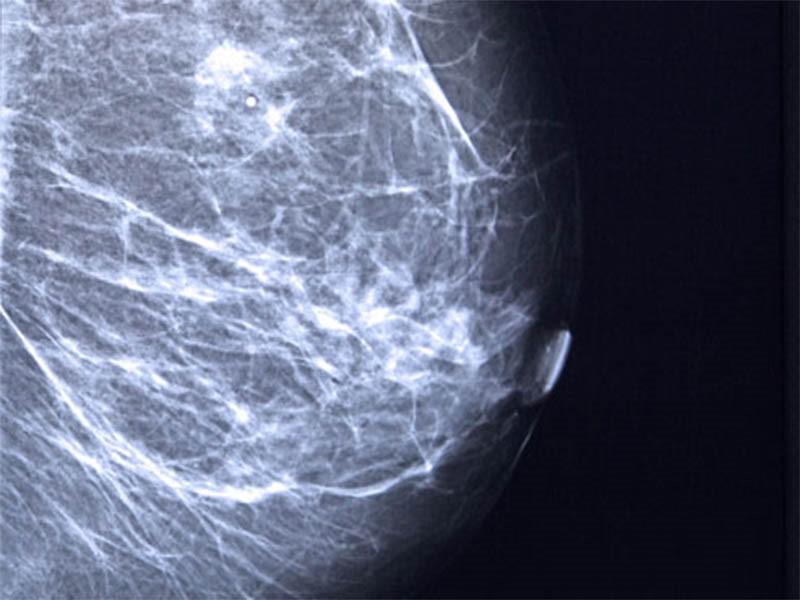

Chụp X-quang tuyến vú là phương pháp phổ biến giúp phát hiện những bất thường và những khối u xuất hiện tại vú trước khi có triệu chứng.

Trong một số trường hợp bất thường hoặc có nguy cơ cao ung thư vú, các bác sĩ có thể chỉ định bệnh nhân thực hiện siêu âm vú hoặc chụp MRI.

Khoảng 80% các trường hợp khối u là lành tính. Chúng thường trở thành những nang vô hại hoặc có liên quan tới những thay đổi về chu kỳ kinh nguyệt. Tuy nhiên, khi phát hiện xuất hiện cục u ở vú, bạn cần phải tới ngay các cơ sở y tế để thăm khám, tìm ra nguyên nhân và có phương pháp điều trị kịp thời.

Sinh thiết vú chính là bước cuối cùng được thực hiện để kết luận ung thư vú.